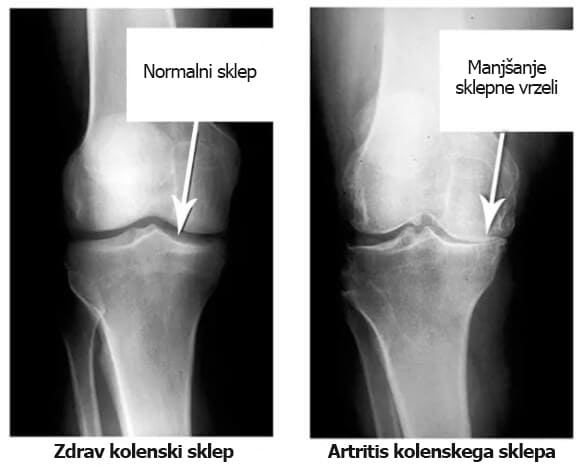

Če pogledamo te rentgenske slike, vidimo, da na desni sliki ni sklepne votline – kosti drgnejo druga ob drugo, kar bolniku povzroča neznosne bolečine. Ta proces je zelo težko zaustaviti!